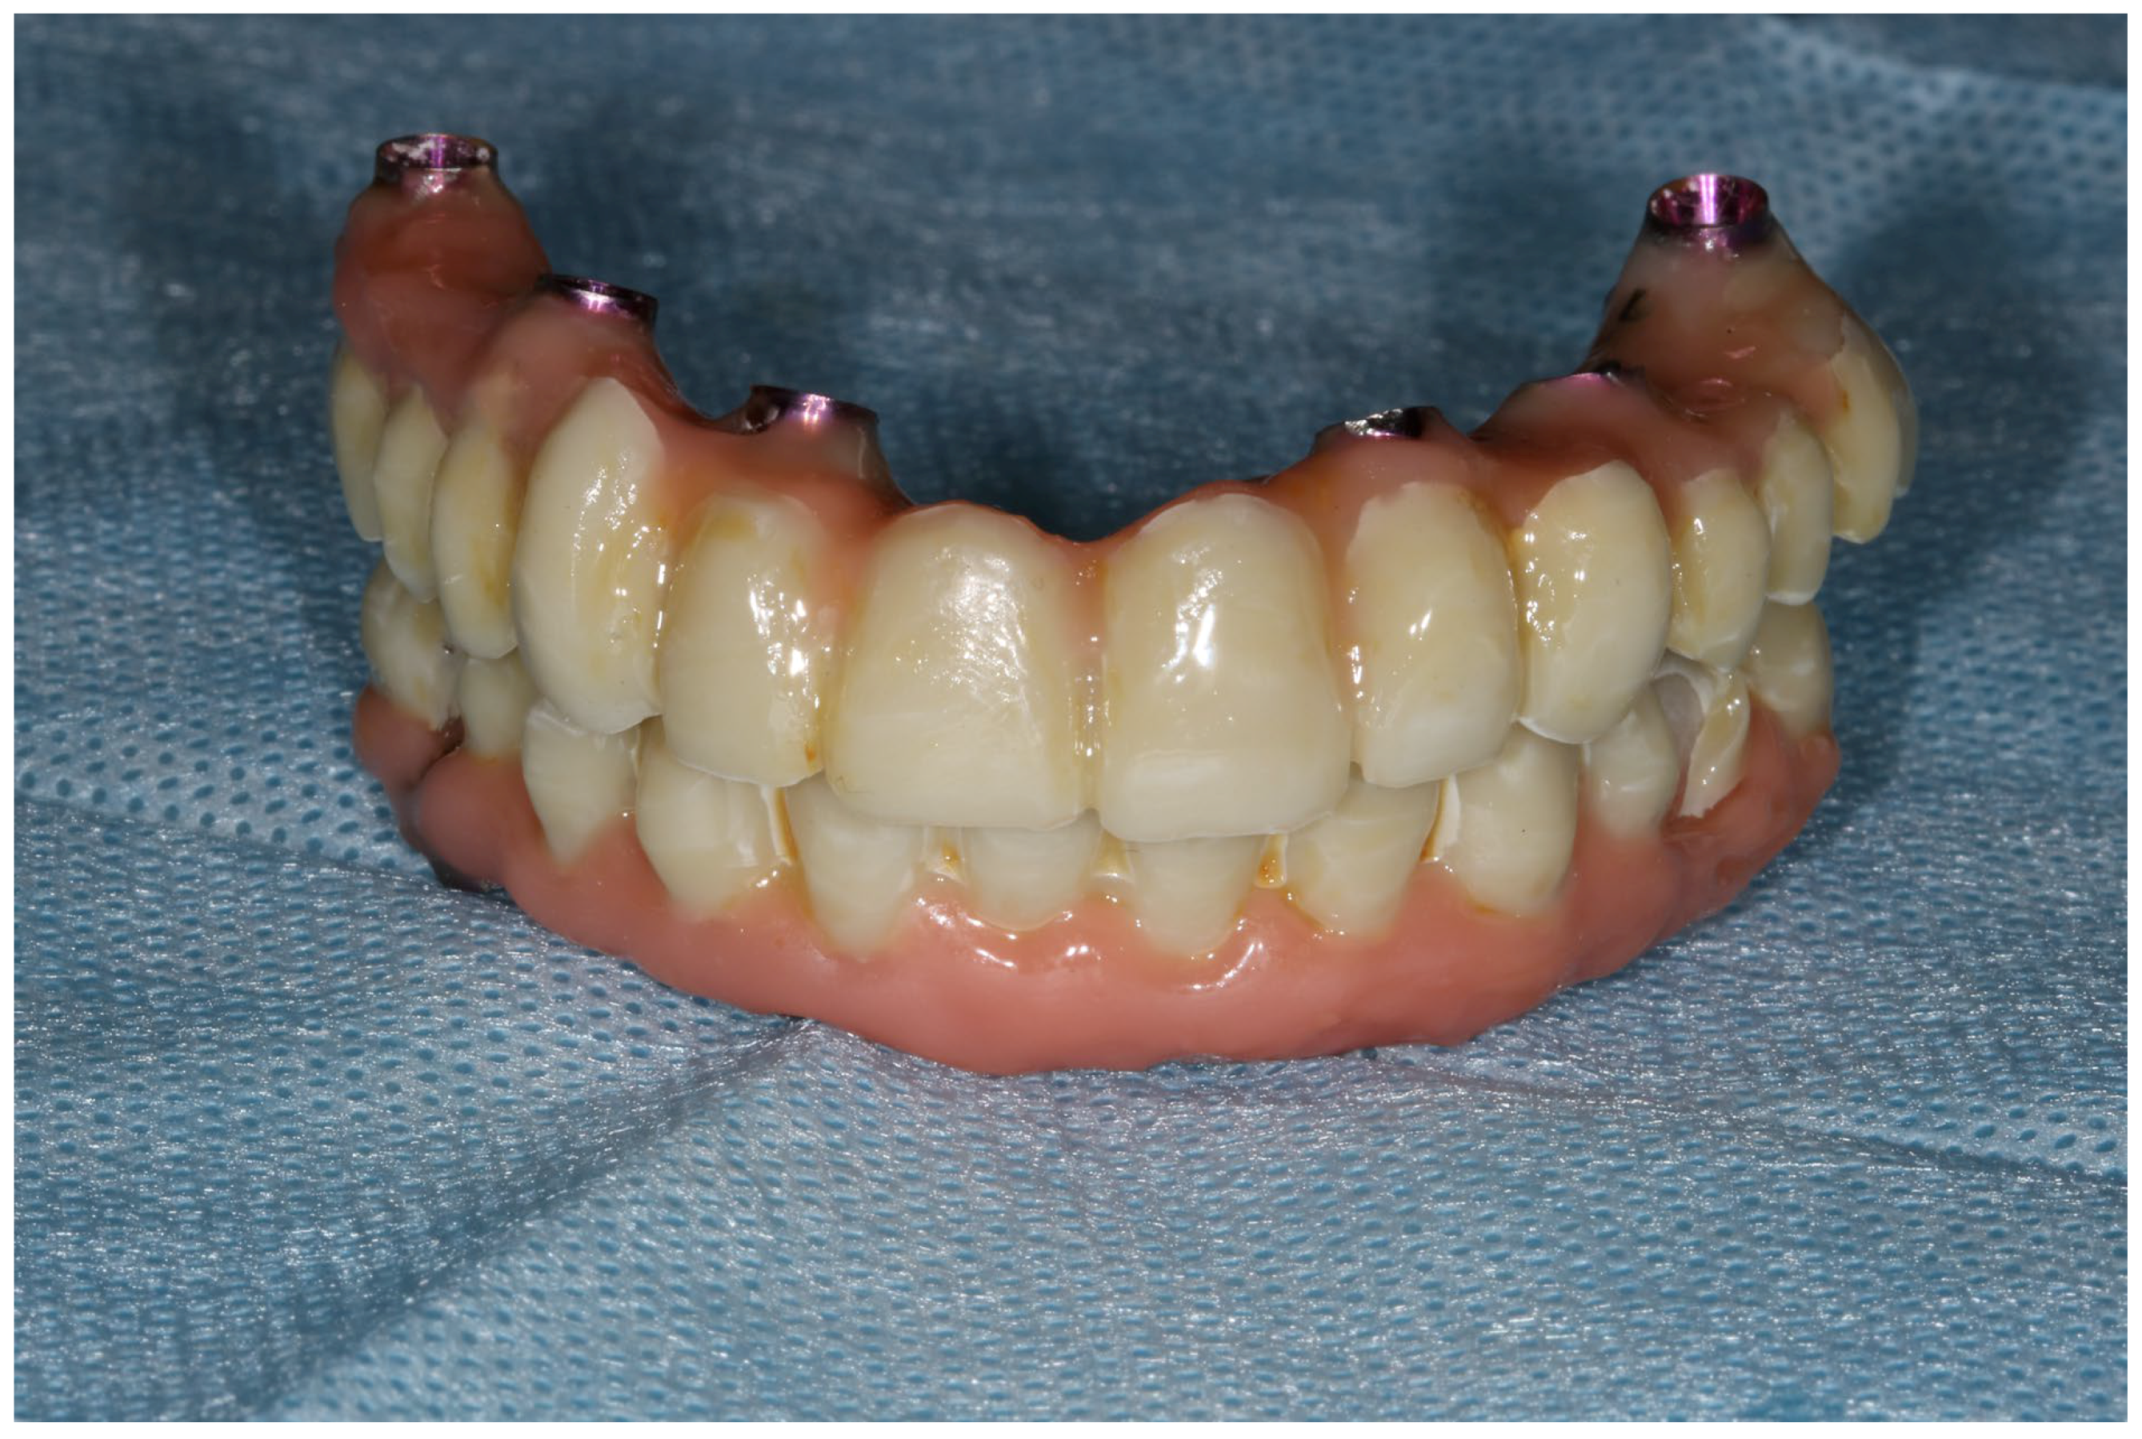

- The conduction of a Sheffield passive fit test of 3D-printed try-ins on a milled titanium bar.

- Final restoration delivery with occlusal equilibration.